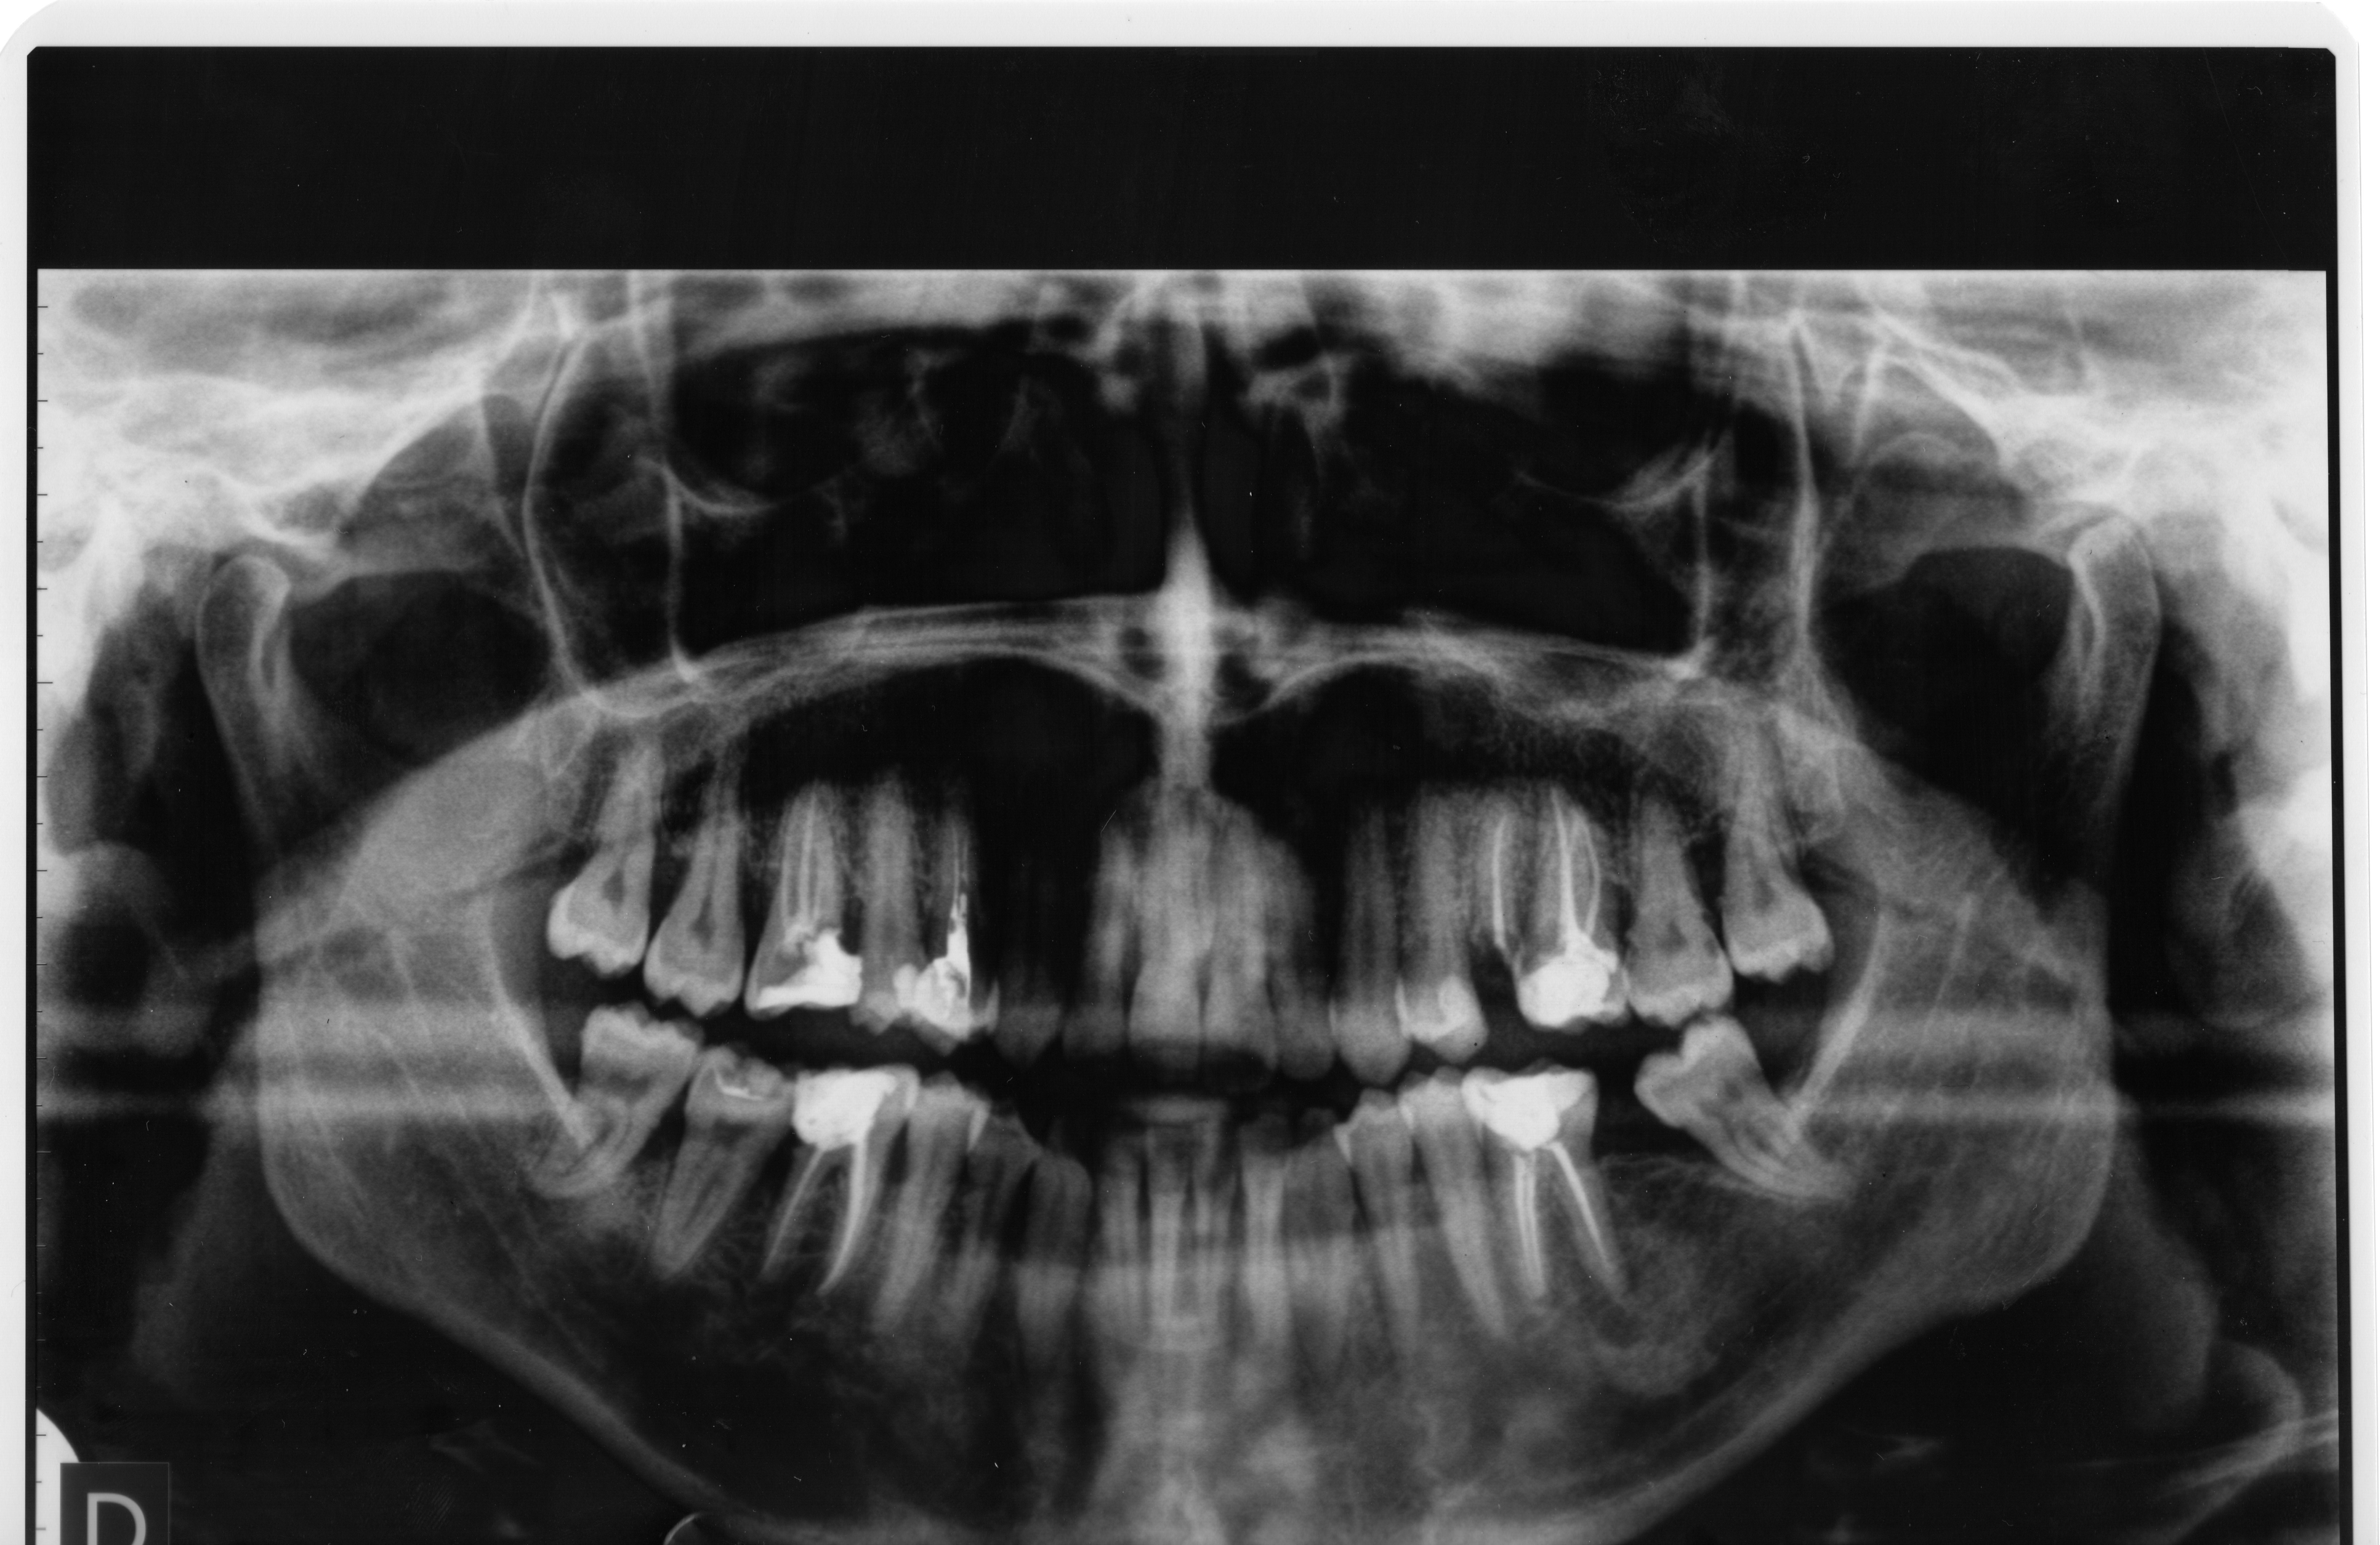

Buongiorno, ringrazio molto tutti i dottori che hanno risposto alla mia domanda relativa al click che sento quando apro la bocca. Ho colto l'occasione per allegarvi una panoramica della mia bocca, risalente al mese di giugno 2011. Il dente del giudizio superiore sinistro che vedete, adesso non c'è più. L'ho tolto ad agosto